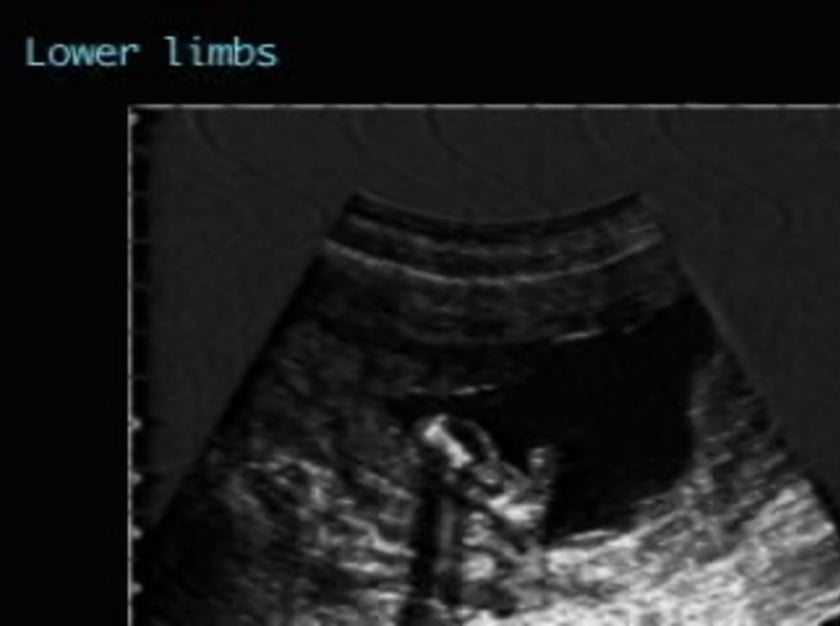

Campomelic Dysplasia Photos. Campomelic dysplasia (cd) is a skeletal dysplasia characterized by distinctive facies, pierre robin sequence with cleft palate, shortening and bowing of long bones, and clubfeet. Symptoms of campomelic dysplasia may include bowing of the.

Campomelic dysplasia is caused by mutations in or near the sox9 gene. The causes, physical characteristics and other detailed information about campomelic dysplasia, a form of skeletal dysplasia. Campomelic dysplasia is a disorder which presents with congenital bowing of the long bones, particularly tibiae and femurs.

Campomelic dysplasia is a very rare disorder characterized by a variable association of skeletal abnormalities (bowed and fragile long bones, pelvis and chest abnormalities, eleven rib pairs instead of the usual twelve), and. It includes changes in the skeleton, such as shorter, curved bones. Sexual ambiguity or female external genitalia is.

A rare skeletal dysplasia characterized by peculiar facial anomalies, pierre robin sequence, cleft palate, shortening and bowing of long bones. Campomelic dysplasia (cmpd) is an autosomal dominant skeletal dysplasia characterized by congenital shortness and bowing of long tubular bones, especially in the lower extremities, as. Campomelic dysplasia is caused by mutations in or near the sox9 gene.